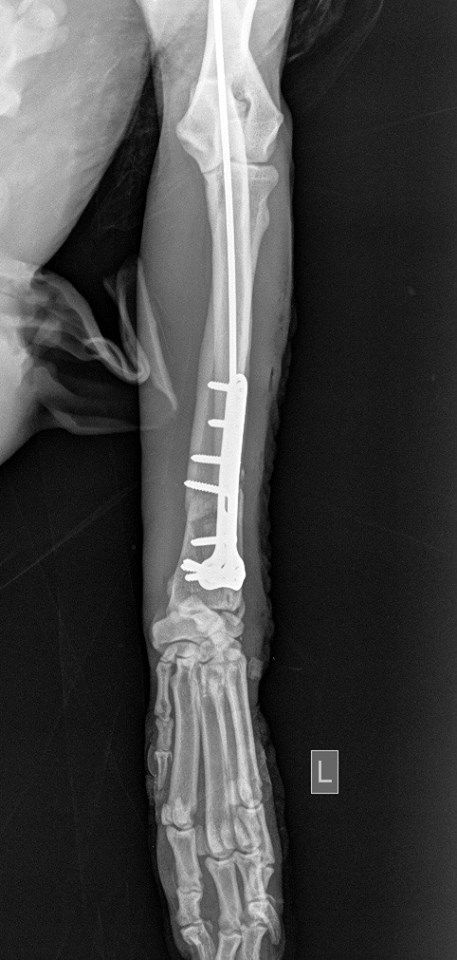

Η κα Μακρή δημοσίευσε σήμερα στο facebook την γνωμάτευση του κτηνιάτρου σχετικά με την εξέλιξη της υγείας του ζώου. Σε αυτή αναφέρεται ότι: «Ο σκύλος έφερε συντριπτικά ενδοαρθρικά κατάγματα με μετατόπιση στο κάτω τρίτο του αριστερού αντιβραχίου και στο κάτω τρίτο του αριστερού μηριαίου. Ολοκληρώθηκε με επιτυχία η πρώτη χειρουργική επέμβαση που αφορούσε την ανάταξη και οστεοσύνθεση του αριστερού αντιβραχίου. Λόγω της σοβαρότητας του κατάγματος η διάρκεια της χειρουργικής επέμβασης ήταν 4 ώρες και 25 λεπτά και ο σκύλος ανένηψε φυσιολογικά».